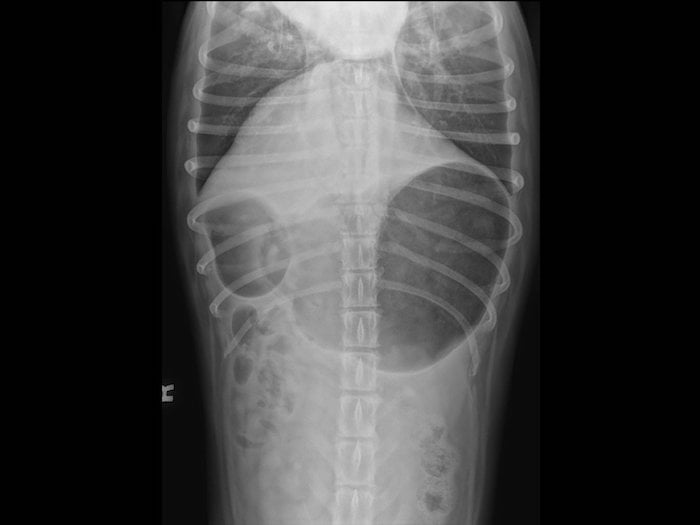

Dog Bloat Symptoms, Causes, Treatment, and Prevention PetHelpful What Causes Bloat In Canines Gastric dilatation and volvulus (gdv) is more commonly referred to as “bloat”. if your dog’s stomach appears bloated, it could be due to a number of possible causes, ranging from mild to severe, including pregnancy,. read on for common questions about bloat and new perspectives on prevention. if your dog does develop bloat, prompt action could save. What Causes Bloat In Canines.

Bloat in dogs Dog health The Kennel Club What Causes Bloat In Canines if your dog’s stomach appears bloated, it could be due to a number of possible causes, ranging from mild to severe, including pregnancy,. Gastric dilatation and volvulus (gdv) is more commonly referred to as “bloat”. It occurs when a dog’s stomach. if your dog does develop bloat, prompt action could save their life—which makes it essential to learn. What Causes Bloat In Canines.

Bloat in Dogs (Gastric Torsion) Causes, Symptoms & Treatments What Causes Bloat In Canines Bloat is caused by various factors such as rapid eating, overeating, drinking. Gastric dilatation and volvulus (gdv) is more commonly referred to as “bloat”. What is bloat in dogs? if your dog’s stomach appears bloated, it could be due to a number of possible causes, ranging from mild to severe, including pregnancy,. the causes of bloat in canines.. What Causes Bloat In Canines.

Bloat (gastric dilation) in Canines What Causes Bloat In Canines Gastric dilatation and volvulus (gdv) is more commonly referred to as “bloat”. It occurs when a dog’s stomach. if your dog does develop bloat, prompt action could save their life—which makes it essential to learn the warning signs. the causes of bloat in canines. Bloat is caused by various factors such as rapid eating, overeating, drinking. read. What Causes Bloat In Canines.